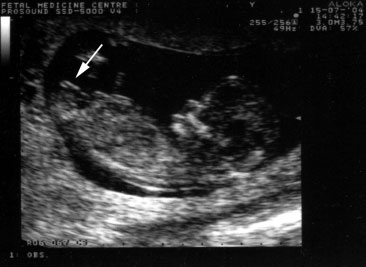

Anita's dilemma is not uncommon. Across India, women often grapple with health concerns that remain unaddressed due to lack of awareness or access to reliable healthcare services. One major issue affecting women is the difficulty in accessing timely and precise diagnostic services, such as ultrasounds, which are crucial in identifying and managing various health conditions. From monitoring pregnancy to diagnosing gynecological issues, ultrasounds play a pivotal role in women's health.

This is where female ultrasound services make a significant difference. These services offer a safe, non-invasive, and reliable diagnostic tool to address the myriad health problems women face. For Anita, the ability to undergo an ultrasound at a specialized clinic meant the world. It was not just about receiving a diagnosis; it was about gaining peace of mind and the empowerment that comes from understanding one's own body.

One inspiring case study involves Priya, a 28-year-old IT professional from Bangalore. Priya experienced severe abdominal pain and irregular menstrual cycles, which caused her considerable distress. After several months of uncertainty, Priya opted for a female ultrasound at a reputable clinic. The results were prompt and revealed a clear diagnosis of polycystic ovary syndrome (PCOS). Armed with this information, Priya was able to consult with her doctor and begin a treatment plan tailored to her needs. The ultrasound service not only provided clarity but also gave Priya the confidence to take control of her health.